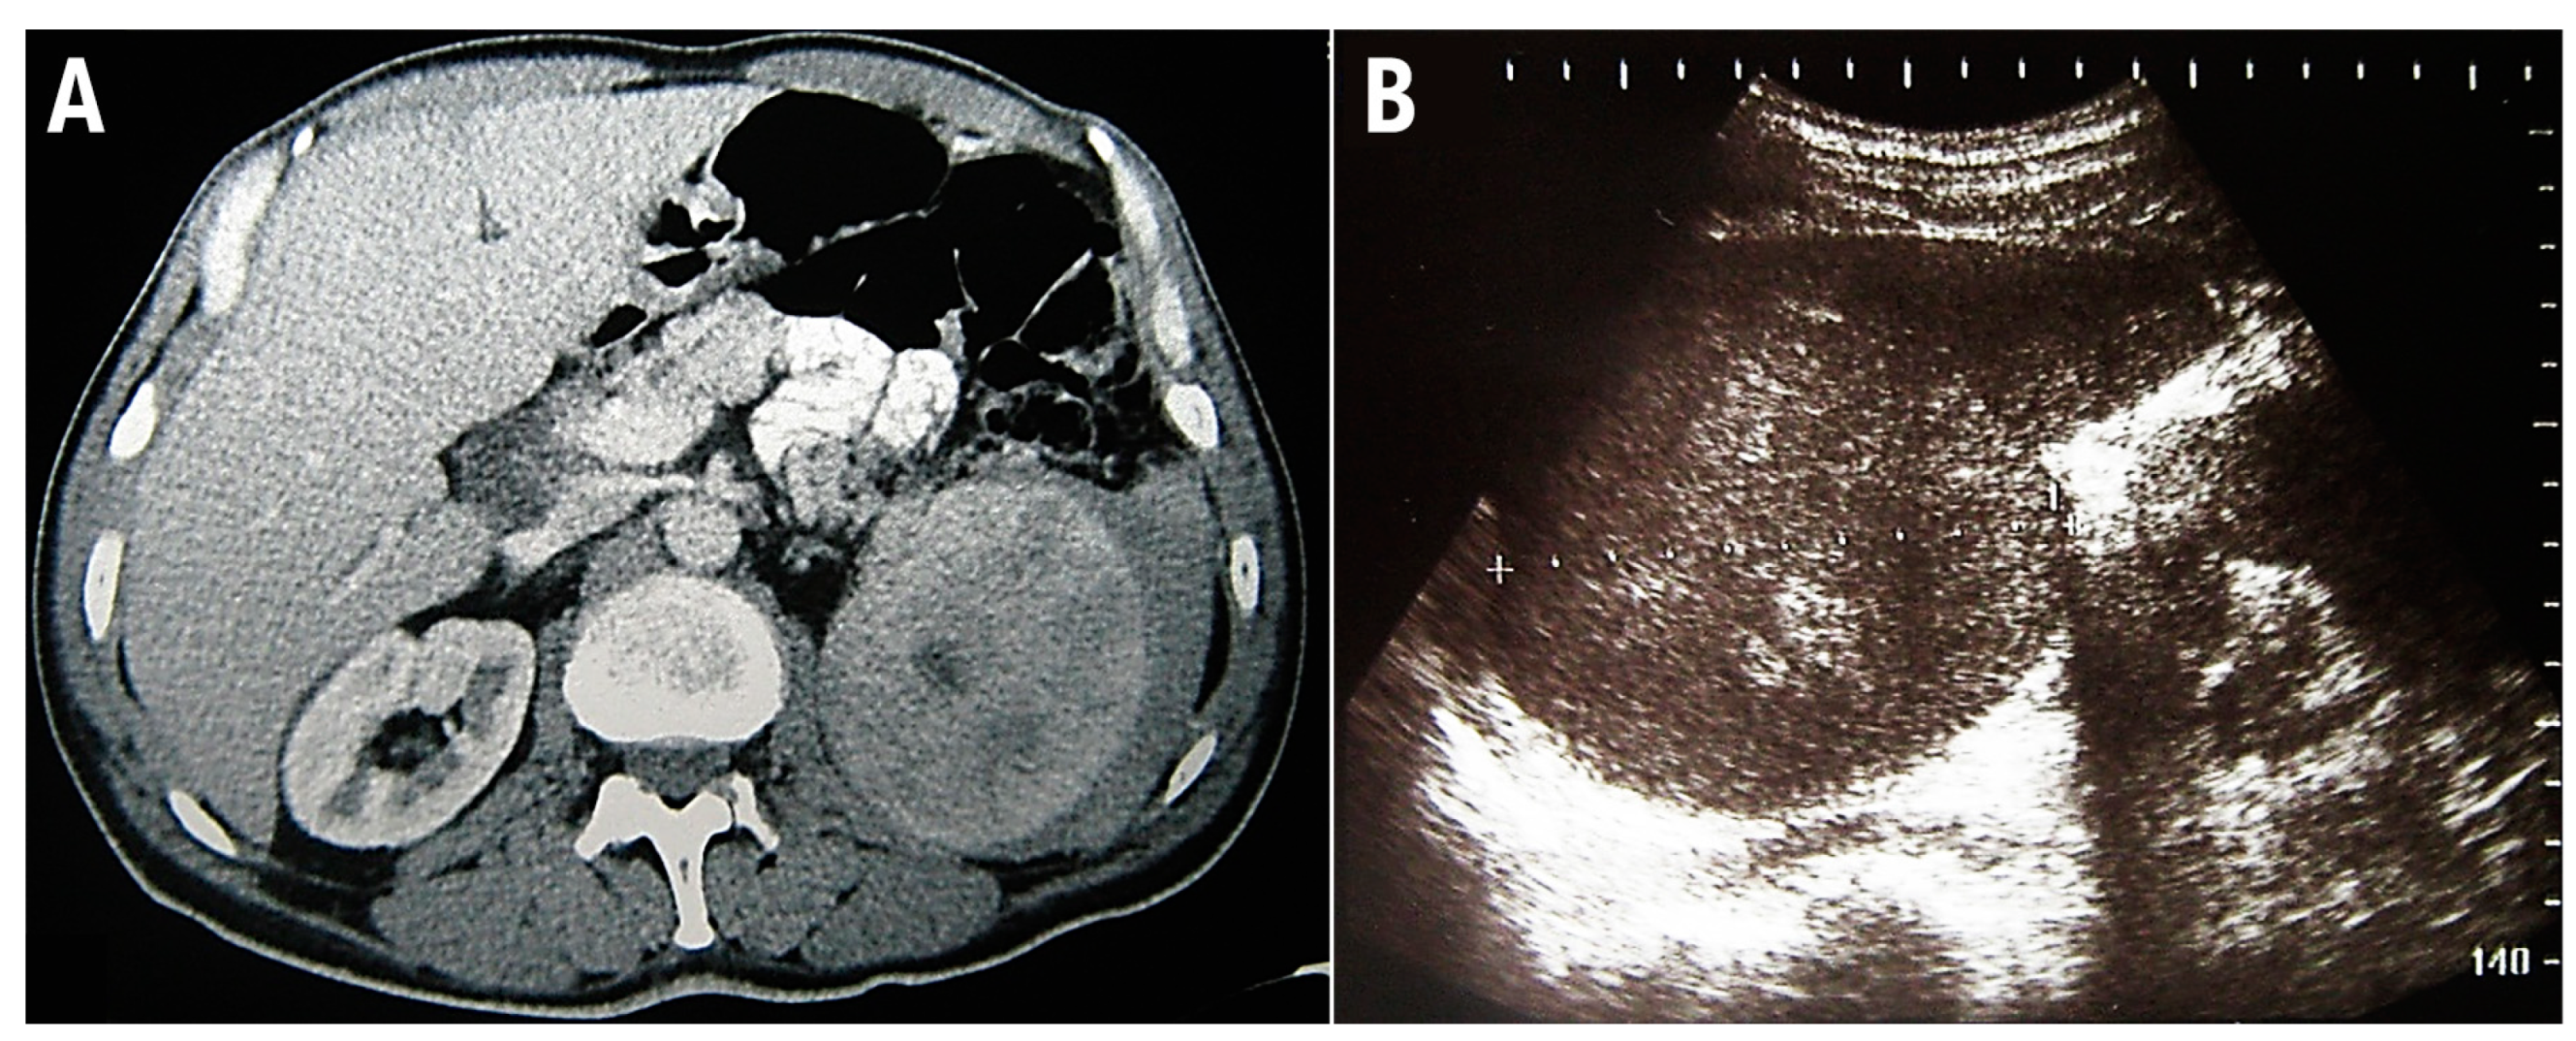

This study conforms to the CARE guidelines [8]. A 48-year-old man was admitted for a prompt surgical consultation at the Clinical Center of Serbia, Belgrade, a clinic for abdominal surgery. Over the previous 3 months, the patient had experienced episodes of abdominal pain, malaise, fever, and repeated nose bleeding accompanied by weight loss of around 20 kg. The patient provided anamnestic information that during the last year he worked on a cruise ship on the Mediterranean route, including North African countries. On admission, no signs of hemorrhagic diathesis were observed. Abdomen ultrasonography and computed tomographic scanning revealed significant splenomegaly (Figure 2).

Figure 2.

Multidetector computed tomography reveals enlarged, inhomogeneous spleen with intraparenchymal confluent zones of lower density, and a small amount of free fluid is present along the lateral contour of the spleen (A). Abdominal ultrasonographic examination shows enlarged spleen with diffusely inhomogeneous parenchyma (B).